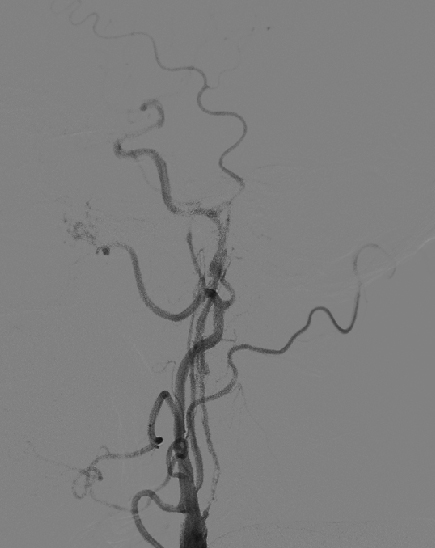

DSA :左侧颈内动脉狭窄。

该患者中老年男性,起病急,反复短暂性脑缺血发作,1年前脑梗死,DSAT提示左侧颈内动脉重度狭窄,手术指证明确,张勤奕教授于2011年11月24日成功为该患者施行颈动脉内膜剥脱术,术后患者恢复良好。